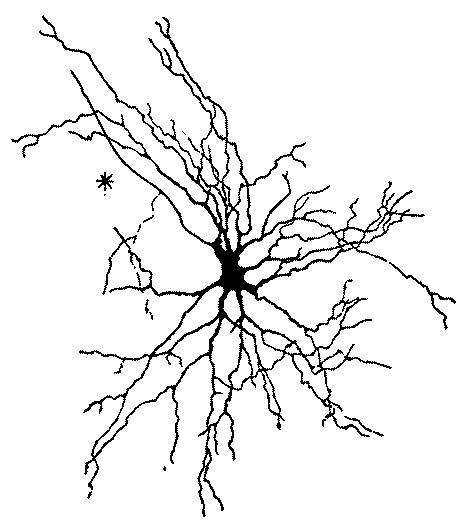

| 2. | Cortex of human brain illustrating complexity of the systems and plexuses of nerve fibers | 109 |

| 3. | Small and medium-sized pyramidal cells of the visual cortex of a child twenty days old | 110 |

| 4. | Series of sections showing the fine nerve endings and branchings of the first and second layer of the visual cortex of a child fifteen days old. | 111 |

| 5. | First, second and third layer of the anterior central convolution of the brain of a child one month old | 112 |

| 6. | Layers of the posterior central or ascending parietal convolution of a new-born child | 112 |

| 7. | Diagram of cells of cerebral cortex | 113 |

| 8. | Scheme of lower motor neuron | 114 |

| 9. | Scheme of the visual conduction paths | 115 |

| 10. | Schematic frontal section through the occipital lobe illustrating manifold connections in a single lobe | 116 |

| 11. | Isolated cell from human spinal cord | 117 |

| 12. | Neuron from the optic lobe of the embryo chick | 118 |

| 13. | Deep layer of giant pyramidal cells of the posterior central or ascending parietal convolution of a child thirty days old | 119 |

| 14. | Pyramidal cell of cerebral cortex of mouse | 119 |

| 15. | Neuroglia cells of the fascia dentata, in the new-born rabbit | 121 |

| 16. | Neuroglia cell from the subcortical layer of the cerebrum from which two processes go to a blood vessel | 122 |

| 17. | Neuroglia cells from the spinal cord | 122 |

| 18. | An artery from the cerebral cortex | 125 |

| 19. | Neuroglia cells of the superficial layers of the brain from an infant aged two months | 126 |

| 20. | Complexity of cell of the central nervous system | 131 |

| 21. | Section through the cortex of the gyrus occipitalis superior | 132 |

| 22. | Motor cell of ventral horn of spinal cord from the human fetus | 133 |